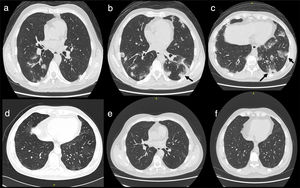

Case 2A 42 years old male patient presented in our facility with acute onset of respiratory symptoms including dry cough, dyspnea and chest pain. The disease onset was preceded by constitutional symptoms fever, anorexia, intense myalgia and weight loss of one month duration. HRCT was ordered and showed widespread pulmonary infiltrates highly suspect of GPA (Fig. 1). c-ANCA was ordered and showed positive results for c-ANCA together with elevated markers of inflammation ESR 1st hour and CRP levels. The patient started with corticosteroid prednisolone 20mg/day/po and MMF 1500mg/day/po. The patient showed dramatic response with much improvement of the respiratory symptoms and other constitutional manifestations. One month after the start of the treatment the HRCT showed almost complete resolution of the pulmonary infiltrates (Fig. 2). The dosage of Prednisolone was tapered to 5mg/day/po and the dosage of MMF was kept the same. During one year of follow up no relapse was reported.